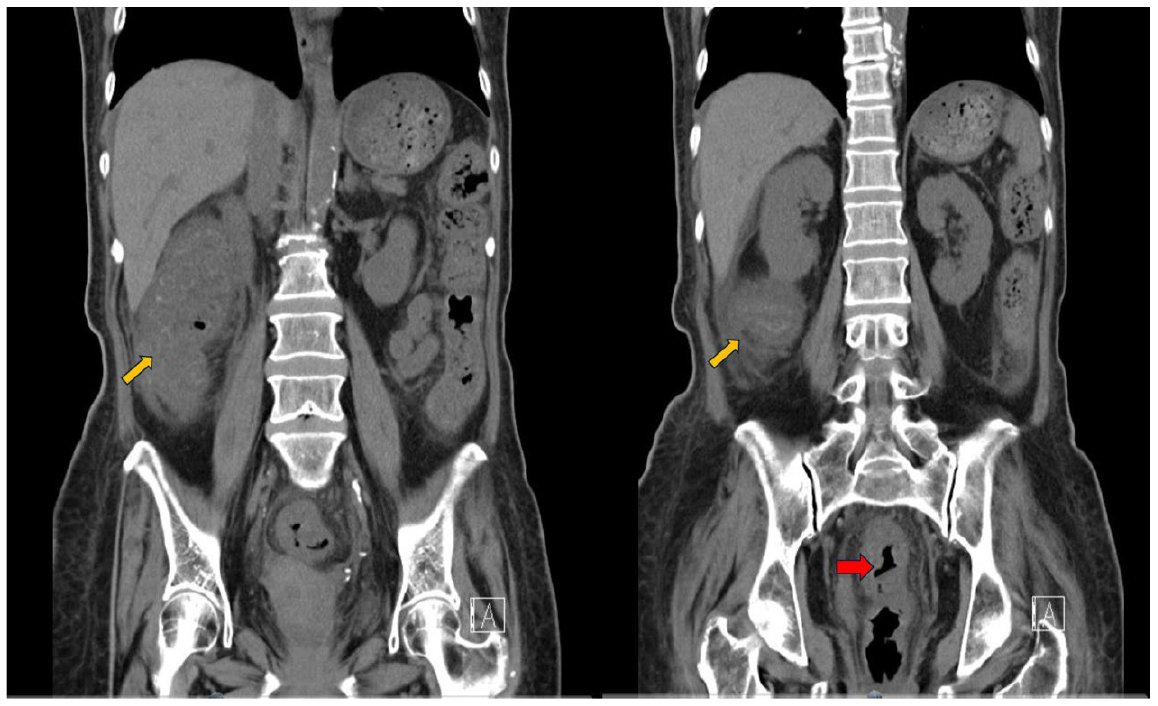

女性長者,肺癌病史目前持續進行化學治療中,因為腹瀉1周合併虛弱無力,急診就醫。檢傷的評估如下: 意識清楚:E4M6V5,血氧濃度:97%,體溫:35.1℃, 脈搏:108 (次/min),呼吸 :18(次/min),血壓:86/49 mmHg 。焦點式身體診察顯示下腹壓痛。抽血報告,如下: 白血球(WBC):3 X10^3/uL, 發炎指數 (CRP): 18.66 mg/dL (正常值<0.3)。由於病人呈現明顯下腹痛和腹膜炎症狀,臨床醫師安排腹部電腦斷層,但是因為病人腎功能不佳,影像的呈現屬於未施打靜脈顯影劑 (contrast medium)的條件(圖一)。

圖一腹部電腦斷層(未施打靜脈顯影劑) (縱切面)。左圖,整段升結腸和直腸腸壁明顯腫脹,腸壁的腫脹,呈現相較“不規則均勻環狀的腫脹“ (紅色箭頭)。右圖,升結腸周邊的脂肪組織呈現腫脹發炎反應,呈現相較高亮度的變化(本來是低亮度(黑色)) (Pericolic fat stranding)(黃色箭頭)。